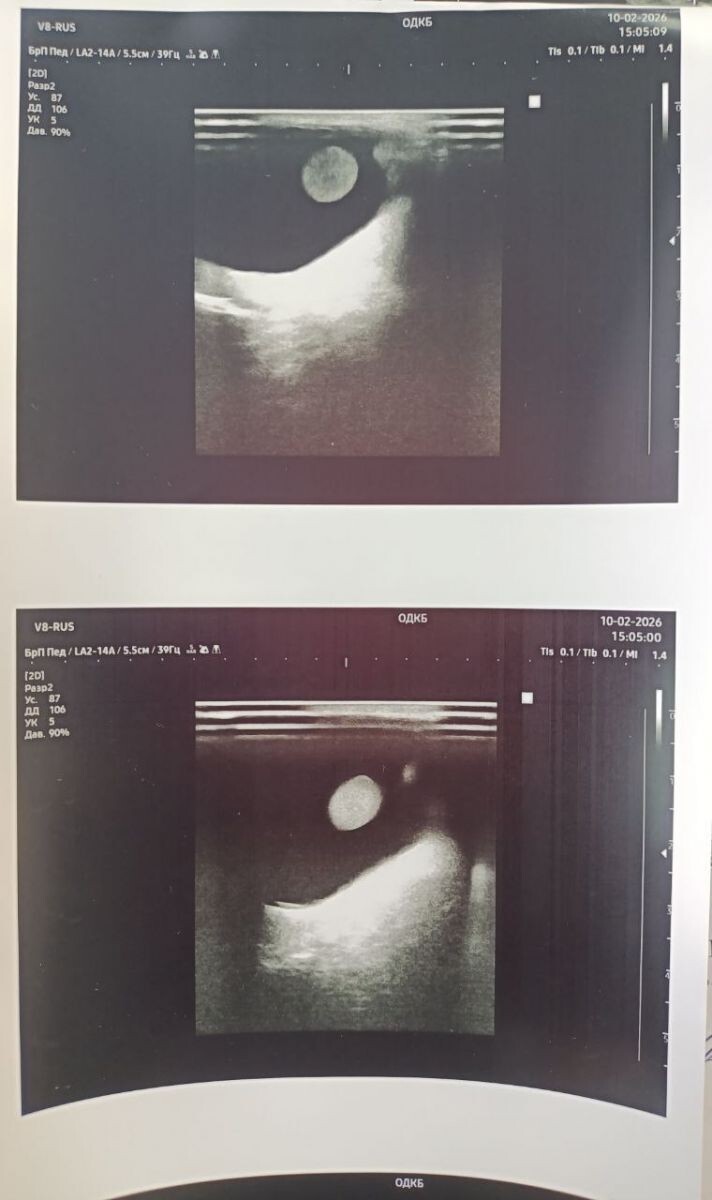

Врачи первого педиатрического отделения Областной детской клинической больницы выявили у девочки-пациентки редкое заболевание — аутоиммунный гепатит.

Как сообщили в ОДКБ, девочку госпитализировали с характерными симптомами: сильной слабостью, болями в животе, пожелтением кожи и серьезными отклонениями в биохимических показателях печени. После клинико-лабораторных и инструментальных обследований врачи заподозрили болезнь. Диагноз позднее подтвердили специалисты РДКБ.